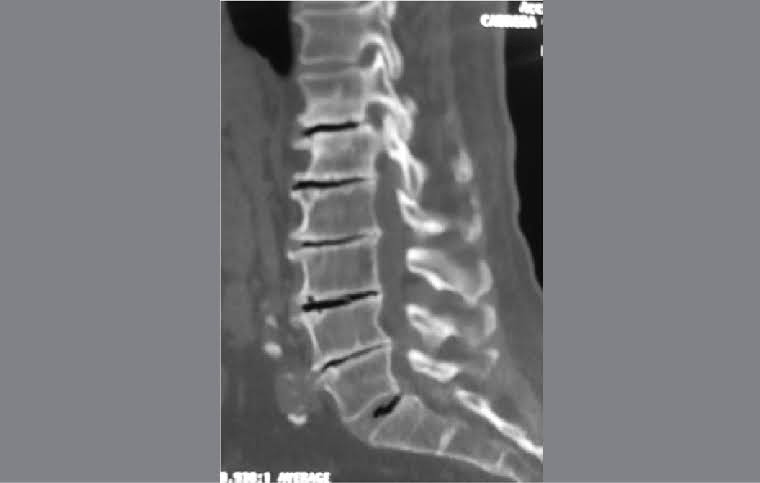

Name of condition seen in these images

https://photos.app.goo.gl/G7V6PXx4Yhi1yyix6

What is a syrinx?